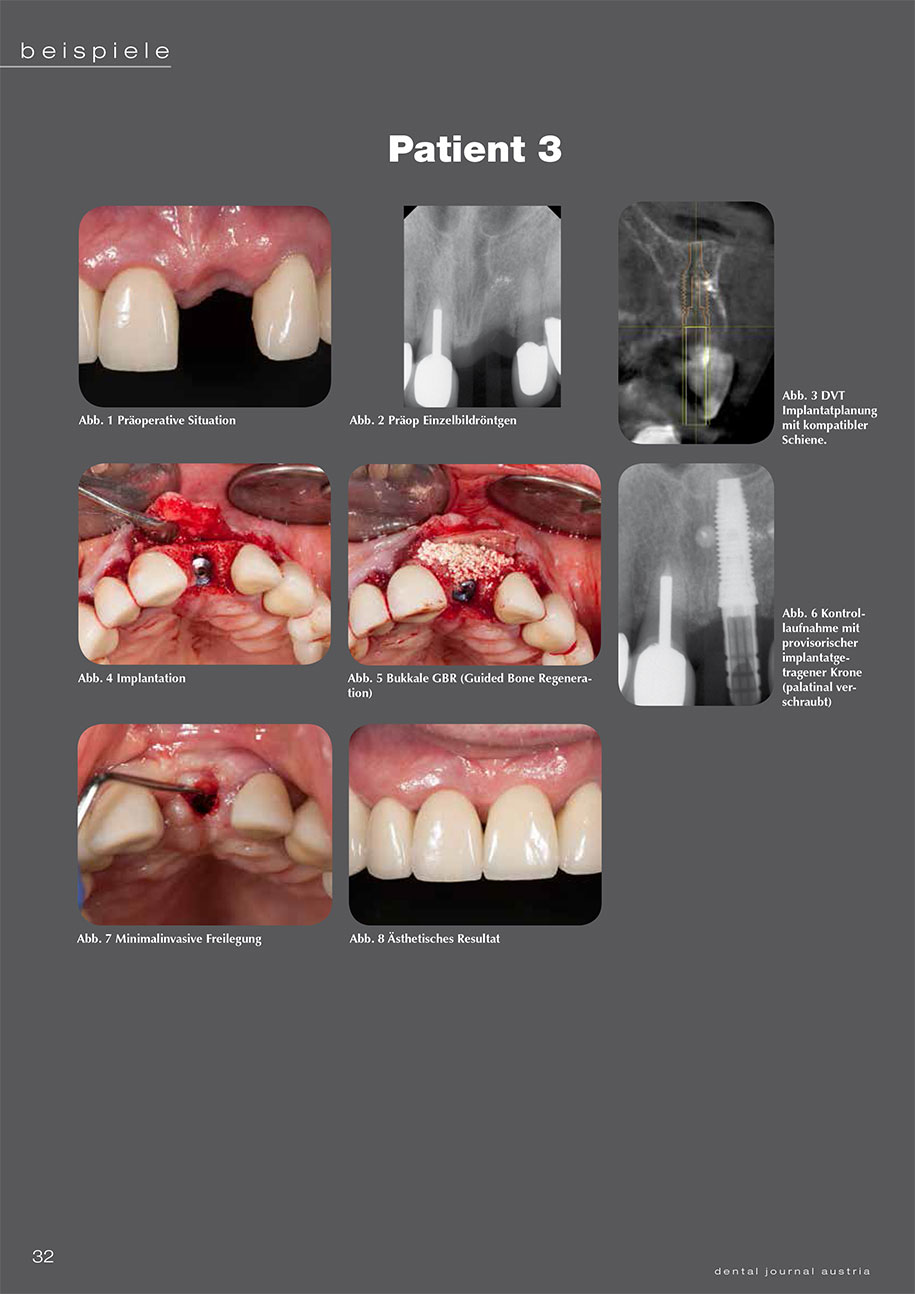

4 Patientenbeispiele